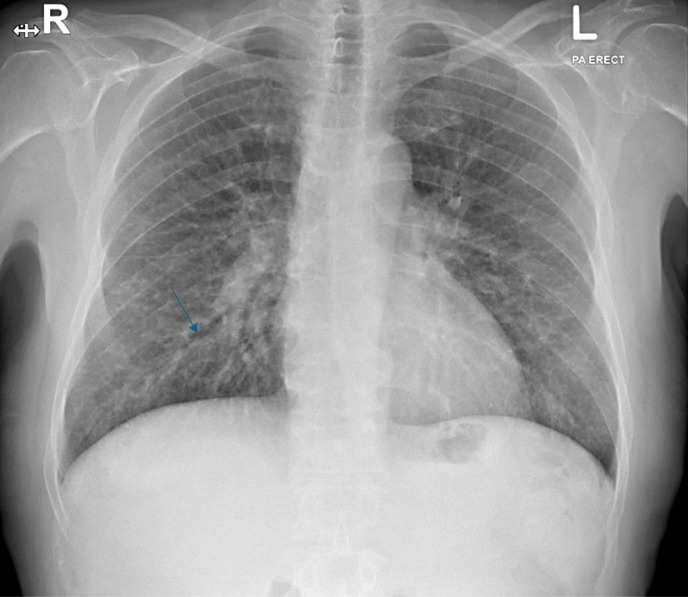

Case presentation: A 60-year-old male patient with multiple comorbidities presented with fever, chills, and cough for 1 day. In the emergency department, he tested positive for COVID-19 by PCR and his chest X-ray revealed features suggestive of pulmonary edema. The patient was intubated and admitted to the Medical Intensive Care Unit (MICU) for management of COVID-19 pneumonia with pulmonary edema. During hospitalization, he developed cardiac complications that required targeted management. Approximately 1 week after admission, his liver enzymes began to rise. Although drug-DILI was initially suspected and hepatotoxic medications were discontinued with the initiation of ursodeoxycholic acid (UDCA), the liver function tests (LFTs) remained elevated. Subsequent magnetic resonance cholangiopancreatography revealed periportal inflammation with intrahepatic biliary dilatation and stricturing, findings consistent with COVID-19 induced cholangiopathy. The UDCA dosage was doubled, resulting in gradual biochemical improvement; however, the patient ultimately discharged against medical advice.